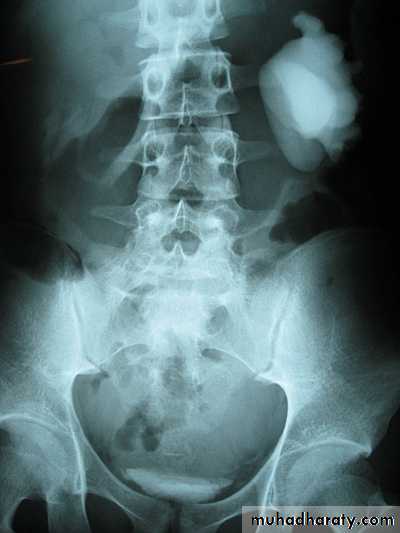

Poly cystic disease

Adult typePresent after the third decade of life , Familial.

Renal parenchyma is replaced by numerous cysts containing fluid , The cysts are of variable size ,

Clinically renal colic, loin mass , heamaturia and hypertension, Renal tissue interposed between the cysts after time dssimcted ended with renal failure

Almost bilateral.

IVU

Large kidney .

Lobulated out-line.

Distortion of pelvi- calyceal system depend on cyst size, number and position.

In advanced cases there is elongation and stretching of minor and major calyces ( spider leg).

In advanced cases IVU shows non-functioning kidney .